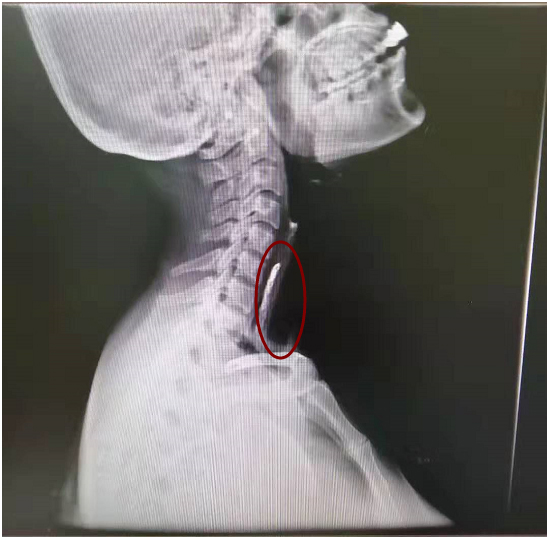

接診后,徐州仁慈醫(yī)院五官科徐曉欣主任檢查發(fā)現(xiàn),雞骨頭已順著喉嚨下滑,便建議張女士做一個上消化道造影,結(jié)果顯示骨頭竟穩(wěn)穩(wěn)嵌在食管上段。

(胃鏡下“元兇”現(xiàn)身)